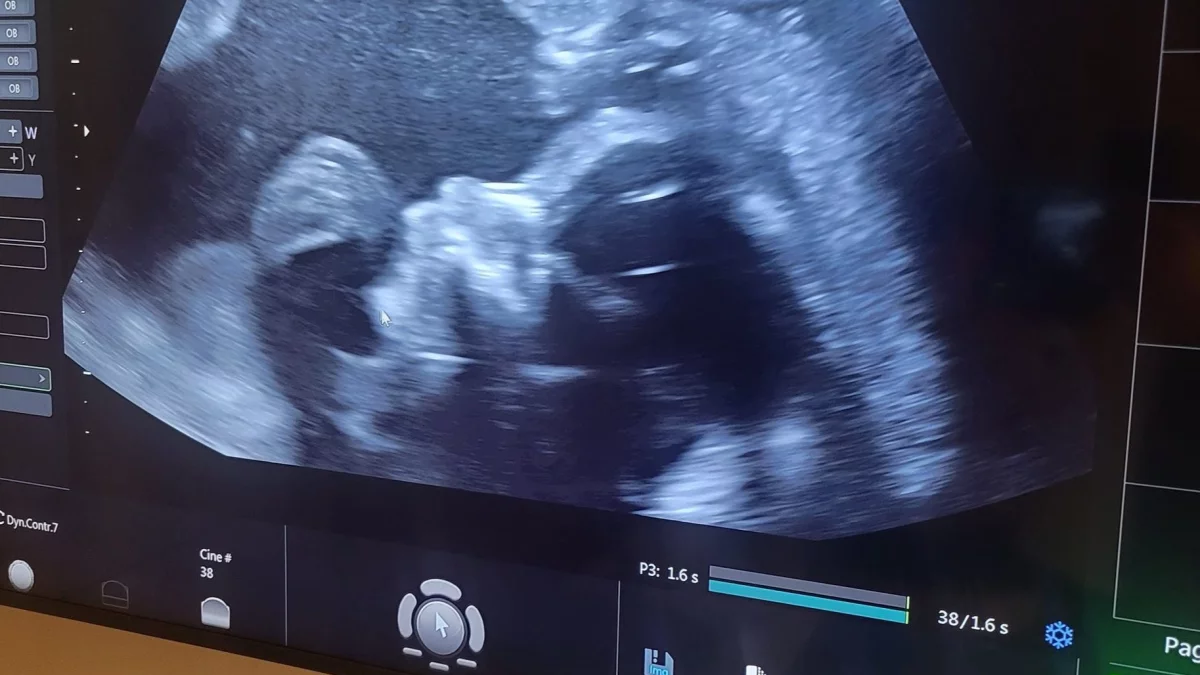

Facebook

ZamojszczyznaMieszkańcy gminy Szczebrzeszyn mogą gratulować. Oto najważniejszy człowiek w gminie, czyli burmistrz Rafał Kowalik, zostanie ojcem. Właśnie się pochwalił i pokazał dowód: - Są takie chwile w życiu mężczyzny, gdy cieszy się na wieść, że zostanie ojcem. Jeszcze bardziej raduje się, gdy wie, że dziecko jest zdrowe a gdy dowiaduje się, że to syn - przekazuje burmistrz Szczebrzeszyna.